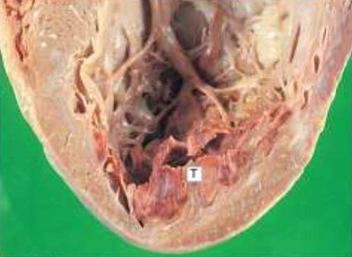

IHD: Myocardial infarction

Acute Myocardial Infarction

Hemopericardium (caused by rupture of infarcts

P= Pericardial sac

B= Filled with blood

H= Surrounding the heart